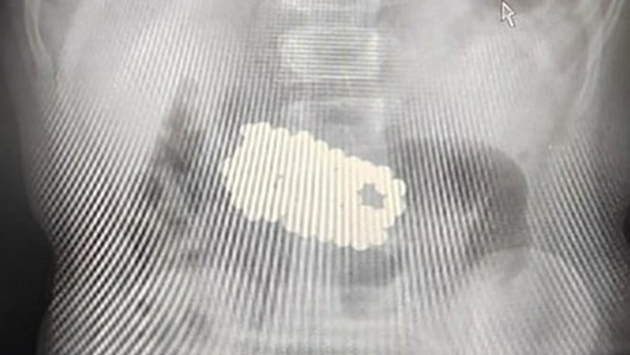

У девочки наблюдались слабость и снижение аппетита, ребенка рвало. Стало известно, что пострадавшая проглотила игрушку-конструктор старшего брата, состоящую из металлических шариков. Врачи обнаружили в желудке ребенка множественные инородные тела.

Руководитель эндоскопического отделения МОНИКИ Елена Вакурова рассказала, что магниты соединились в теле пациентки в единую фигуру. «Под общим наркозом при помощи специального эндоскопического оборудования — корзины Дормиа — инородные тела поэтапно извлечены из желудка. Операция продолжалась около трех часов. Всего из желудка ребенка извлечено 100 магнитных шариков», — сообщила она.